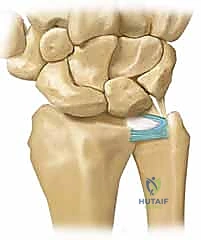

The TFCC is a cartilaginous and ligamentous structure strategically interposed between the ulnar carpus and the distal ulna. It originates distally from the sigmoid notch of the radius – a concave articular surface on the medial aspect of the distal radius – and extends to insert into the base of the ulnar styloid.

The TFCC also attaches to the ulnar carpus via the ulnocarpal ligament complex, which includes the ulnolunate, ulnotriquetral, and ulnar collateral ligaments. These ligaments are not independent structures but rather function as a cohesive unit with the TFCC itself.

The dorsal and volar radioulnar ligaments are fibrous thickenings within the substance of the peripheral TFCC. These are the primary stabilizers of the DRUJ, limiting both rotation and axial migration of the ulna relative to the radius. They are critical for maintaining the congruity and stability of the DRUJ during forearm rotation.